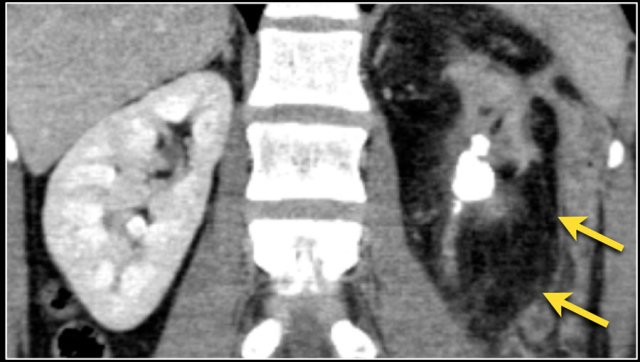

The coronal MR-image shows a tumor thrombus extending into the IVC above the diaphragm (arrows).

A thoracic surgeon will be needed during surgery.

Here a patient with lung cancer.

There is a metastasis in the left kidney and there are multiple lymph node metastases (arrows).

If this was the only presentation, it would be difficult to differentiate from a renal cell carcinoma with lymph node metastases.